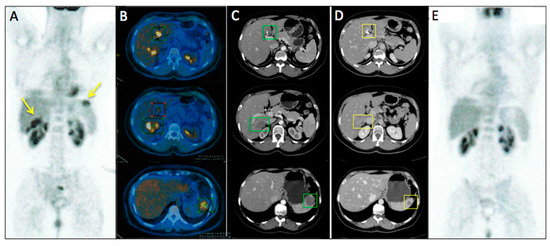

Figure 2 represents an exemplar case of a patient judged as SD at the timepoint-1 evaluation.

Figure 2. A 71-year-old male affected by colorectal cancer with liver metastasis, subjected to 6 cycles of Bevacizumab-based chemotherapy and 10 hyperthermia sessions on the abdomen as second-line. Baseline Multidetector Contrast Enhancement Computed Tomography (MDCT) (A,B) showed metastasis in the II and VIII segment of the liver and caudate lobe (maximum diameter: 47 mm, yellow arrows). Timepoint-1 MDCT (C,D) evaluation demonstrated stable size of liver metastasis (maximum diameter: 44 mm, yellow arrows). According to mRECIST, patient was classified as SD. Ca19.9 and Carcino-Embryonic Antigen (CEA) values evaluated at baseline were 99 UI/mL and 65 ng/mL, respectively; while Ca19.9 and CEA values evaluated at timepoint-1 were 81 UI/mL and 60 ng/mL, respectively. Side effects reported were limited to nausea and mild position-related pain during HT sessions.